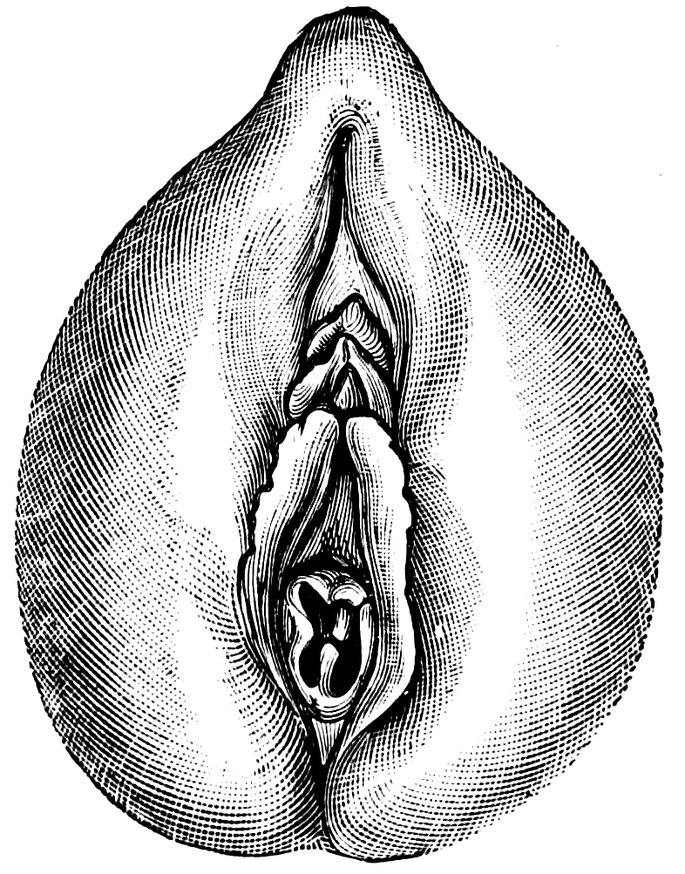

| 12. | Female external genital organs of a virgin | 54 |

| 13. | The external genital organs of a virgin | 55 |

| 48. | The female pudendum, or vulva, with the labia majora | 204 |

| 49. | Vestibule of the vagina, with the labia minora or nymphæ, etc | 205 |